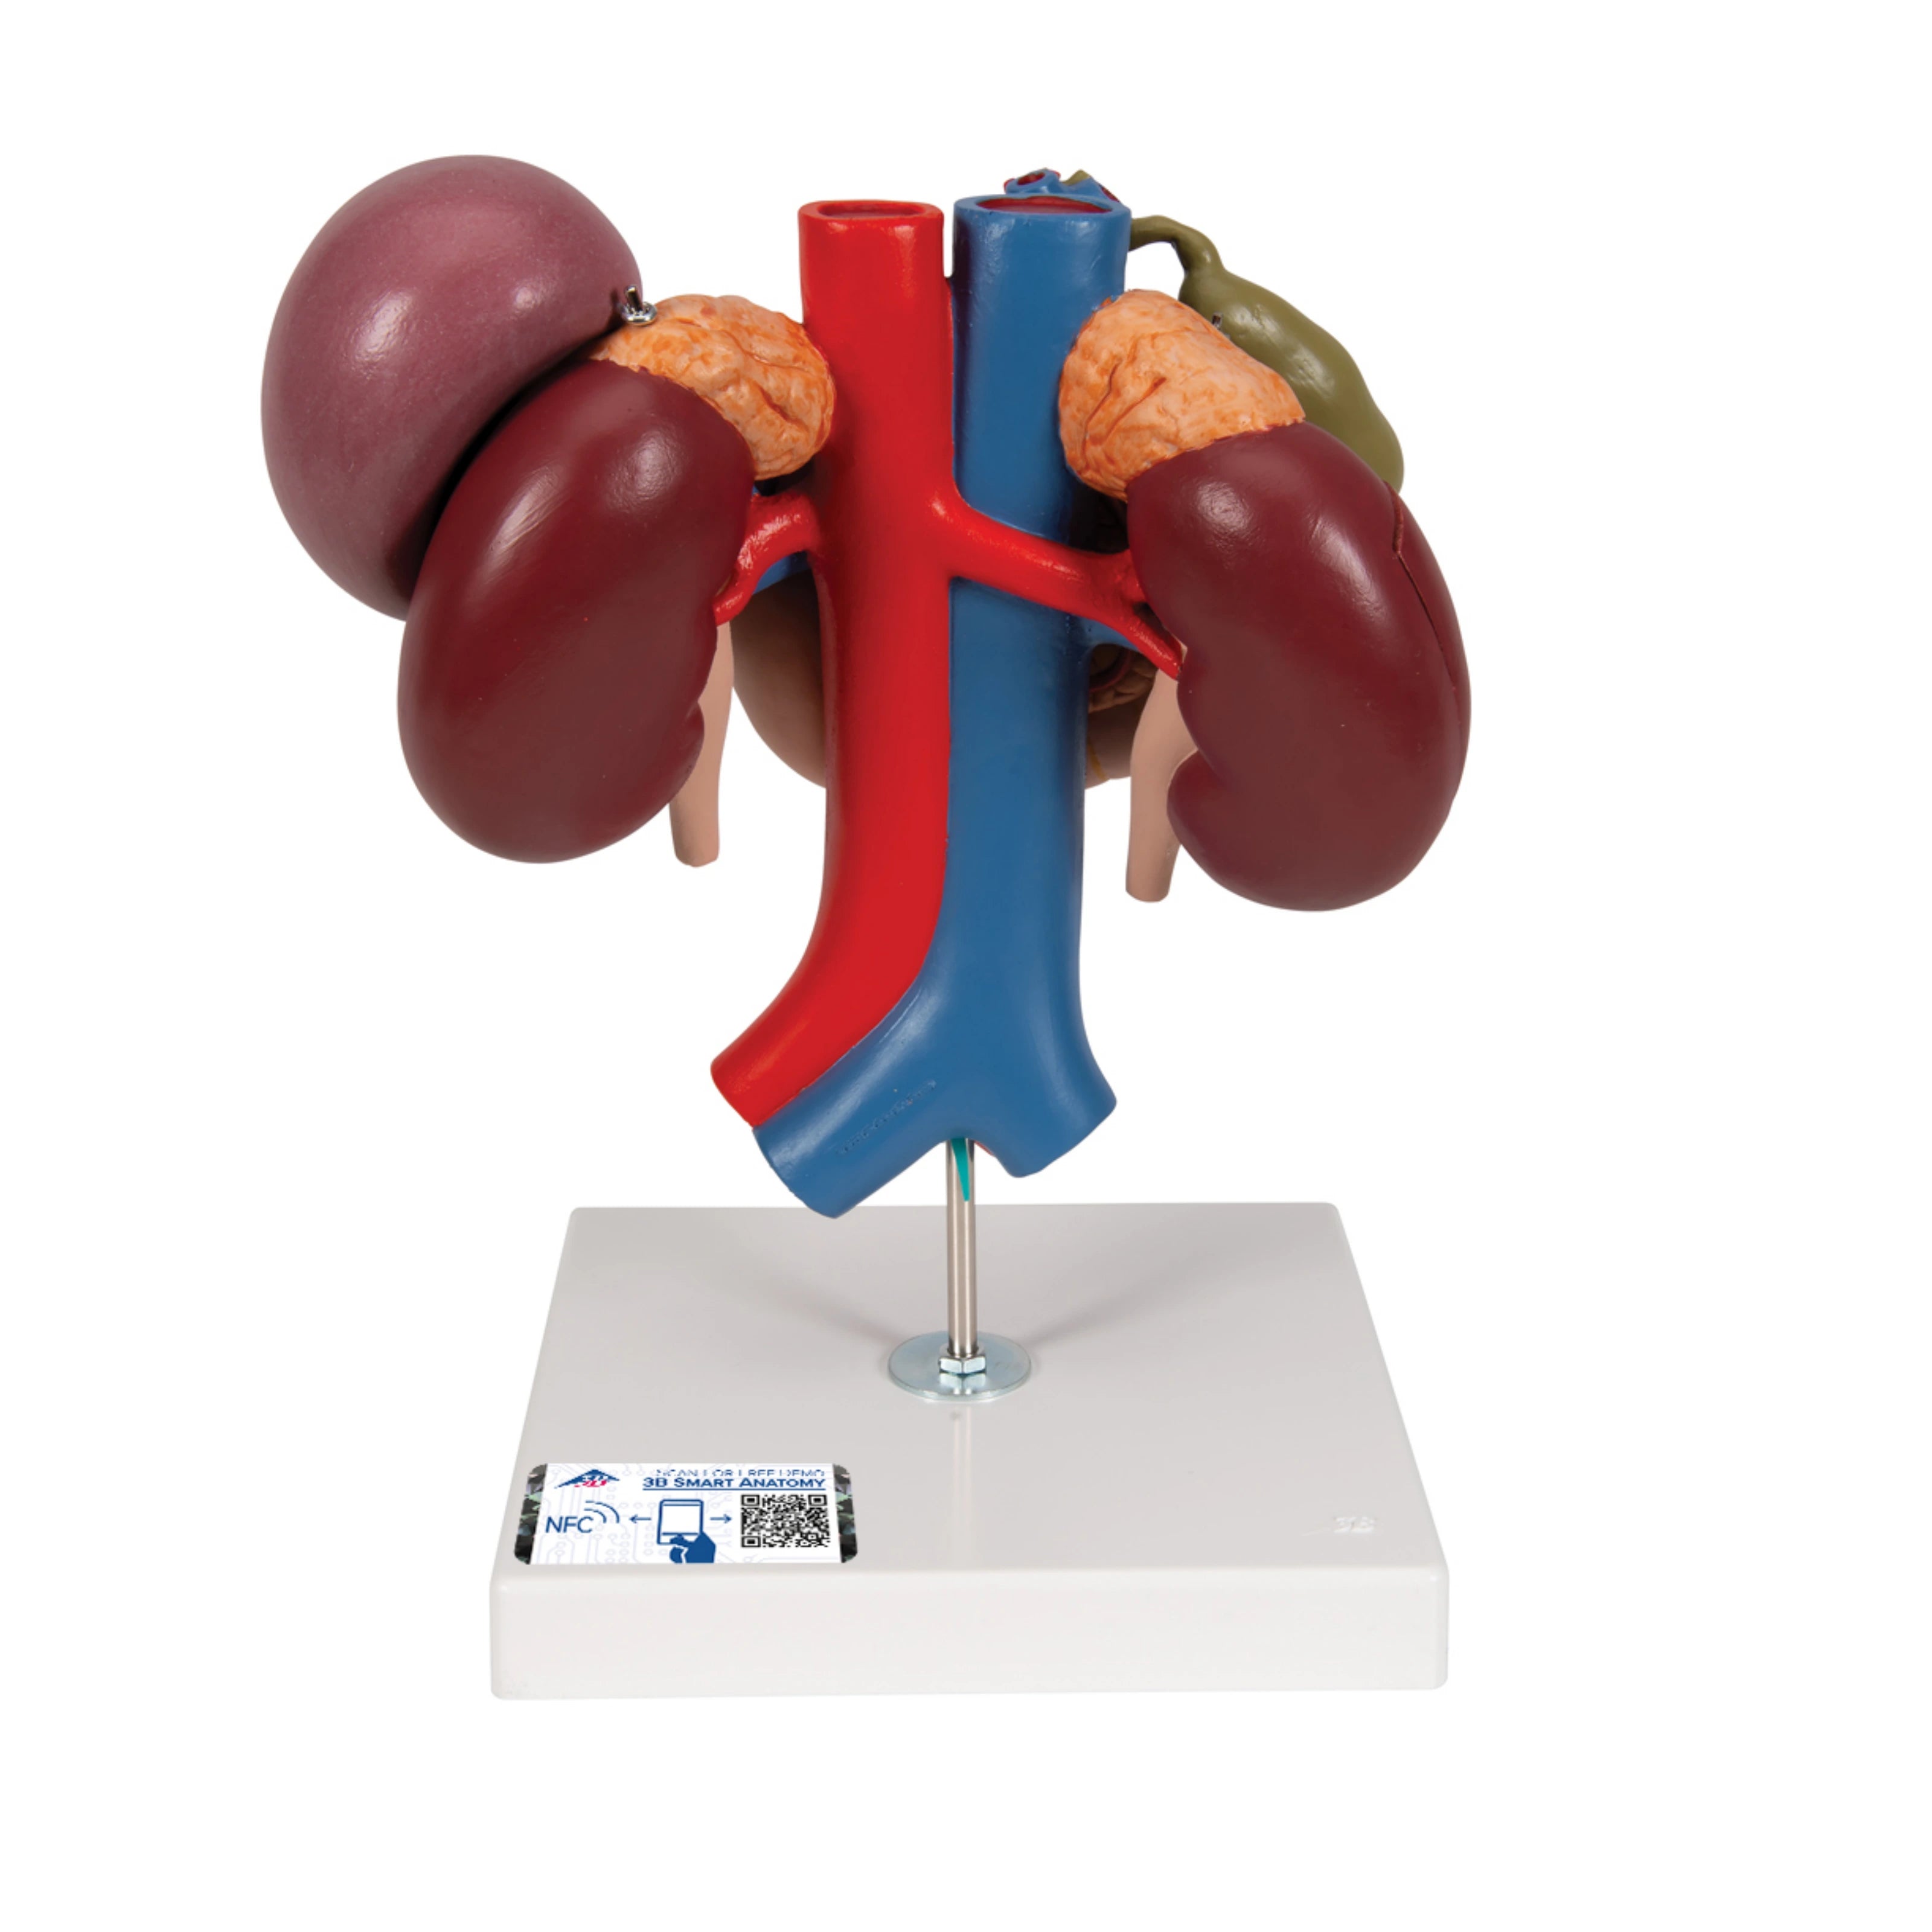

Riñones con Órganos Posteriores del Abdomen Superior (3 Piezas) - 3B Smart Anatomy

Precio de venta$12,993.33